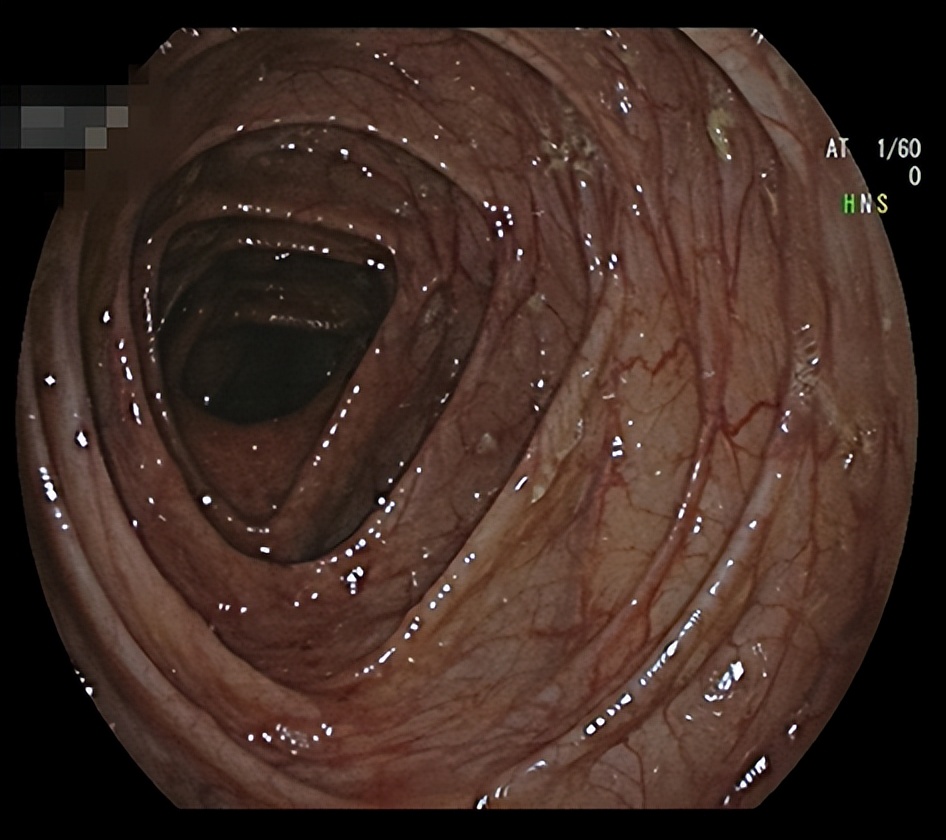

经过新乡医学院第一附属医院炎症性肠病MDT团队讨论,决定为姑娘使用“绿色疗法”,也就是生物制剂。经过治疗后,姑娘的肠子恢复如下: